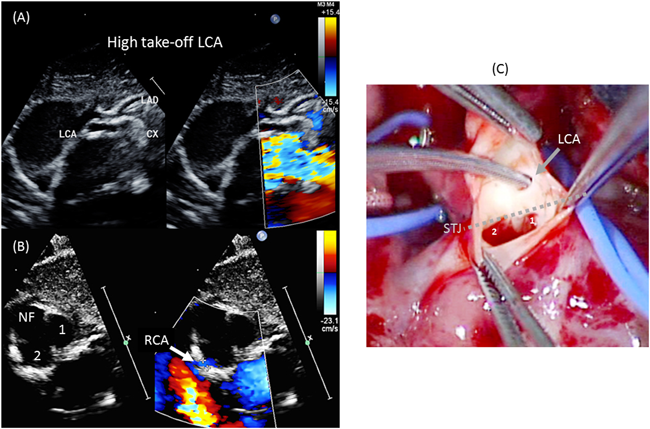

本疾患における冠動脈走行パターンの代表的な表記法にShaher分類とLeiden大学の表記法(Leiden Convention)がある.1966年にShaherらはdTGAの冠動脈パターンを18種類に分類して報告した67).Shaher分類はよく使用される分類法ではあるが,30種類以上存在すると言われるdTGAの冠動脈パターンを全て網羅できない限界を有する.Leiden Conventionは大動脈弁のnon-facing sinus(肺動脈に近接しない大動脈洞)から肺動脈弁を観察したときに,右手側にある大動脈洞をsinus-1(right hand facing sinus),左手側をsinus-2(left hand facing sinus)として各大動脈洞から起始する冠動脈を記載する(左前下行枝=L; 左回旋枝=Cx; 右冠動脈=R).正常の冠動脈起始の表記は{1R; 2LCx}となる(Fig. 7).Fig. 8に静岡県立こども病院にて1998年~2010年の間にJatene手術を施行した66例における冠動脈走行パターンの内訳を示す68).dTGA1型においてはShaher1型{1LCx; 2R}とShaher2A型{1L; 2RCx}で9割を占めるが,dTGA2型とTBAではShaher2AとShaher4 {1LR; 2Cx}の割合が増加した(Fig. 8).また,Jatene術前の冠動脈診断で重要になるのが,高位起始と壁内走行(intramural)の有無である.Fig. 9に術前診断できなかった左冠動脈の高位起始と縦方向壁内走行の症例を示す.術中写真にて大動脈の切開線の延長上に高位起始した左冠動脈の開口部を認める.この冠動脈は高位起始だけでなく,縦方向壁内走行(vertically oriented intramural coronary artery)の異常も合併していた.右冠動脈がsinus-2から起始している断面では大動脈弁の交連が描出されているのに対して,左冠動脈が描出されている断面では大動脈弁の交連が描出されていないことからも高位起始が示唆される.冠動脈壁内走行の大部分は大動脈壁に対して接線方向に走行するが,本症例のように縦方向の壁内走行も存在する.

Fig. 9 A high take-off and intramural left coronary artery in dTGA

(A): A high take-off left coronary artery.(B): Right coronary artery arises from Sinus-2 with antegrade coronary flow at the orifice.(C): The picture during operation: Note the high take-off of the left coronary artery way above STJ. This coronary artery was associated with vertical interamural running.Cx: left circumflex artery; dTGA: d-transposition of great arteries; LAD: left anterior descending artery; LCA: left coronary artery; NF: non-facing sinus; RCA: right coronary artery; STJ: sinotubular junction.